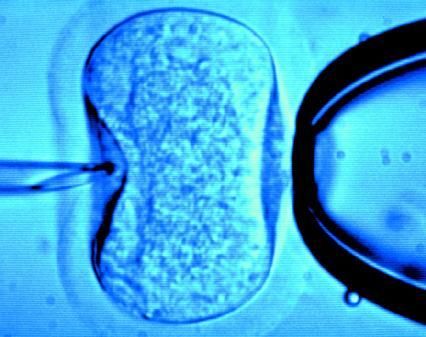

據(jù)英國《每日郵報》1月18日報道,英國一位60歲老婦將成為英國接受試管受精最年長者。這位老婦名叫蘇珊·托勒夫森,是一位退休教師,到今年10月她就滿60歲了。2008年,蘇珊曾去俄羅斯接受試管受精,在英國生下了她的第一個孩子。

倫敦哈利街的私人診所是英國試管嬰兒手術(shù)成功率較高的醫(yī)院之一,醫(yī)生們在上周一同意幫助蘇珊·托勒夫森進(jìn)行第二次人工受孕。通常情況下,私人診所只在特殊情況下給50歲以上的婦女進(jìn)行試管受精,例如,患者仍然有月經(jīng)周期。這件事引起了絕經(jīng)后婦女是否有生育權(quán)利的倫理大討論,現(xiàn)在要求提高生育治療年齡上限的呼聲越來越高。

現(xiàn)在,蘇珊·托勒夫森一家人很幸福,丈夫尼克·邁耶是一位公司經(jīng)理,比她小11歲,他們的女兒今年2歲。專家表示,蘇珊很健康,她的女兒如果能有一個兄弟姐妹會更好,于是蘇珊想再次接受試管受精。《星期日郵報》獲悉,倫敦哈利街私人婦女診所的高級工作人員已經(jīng)同意為蘇珊做試管受精,還決定幫助另一位57歲的老婦受孕。(海瀾)